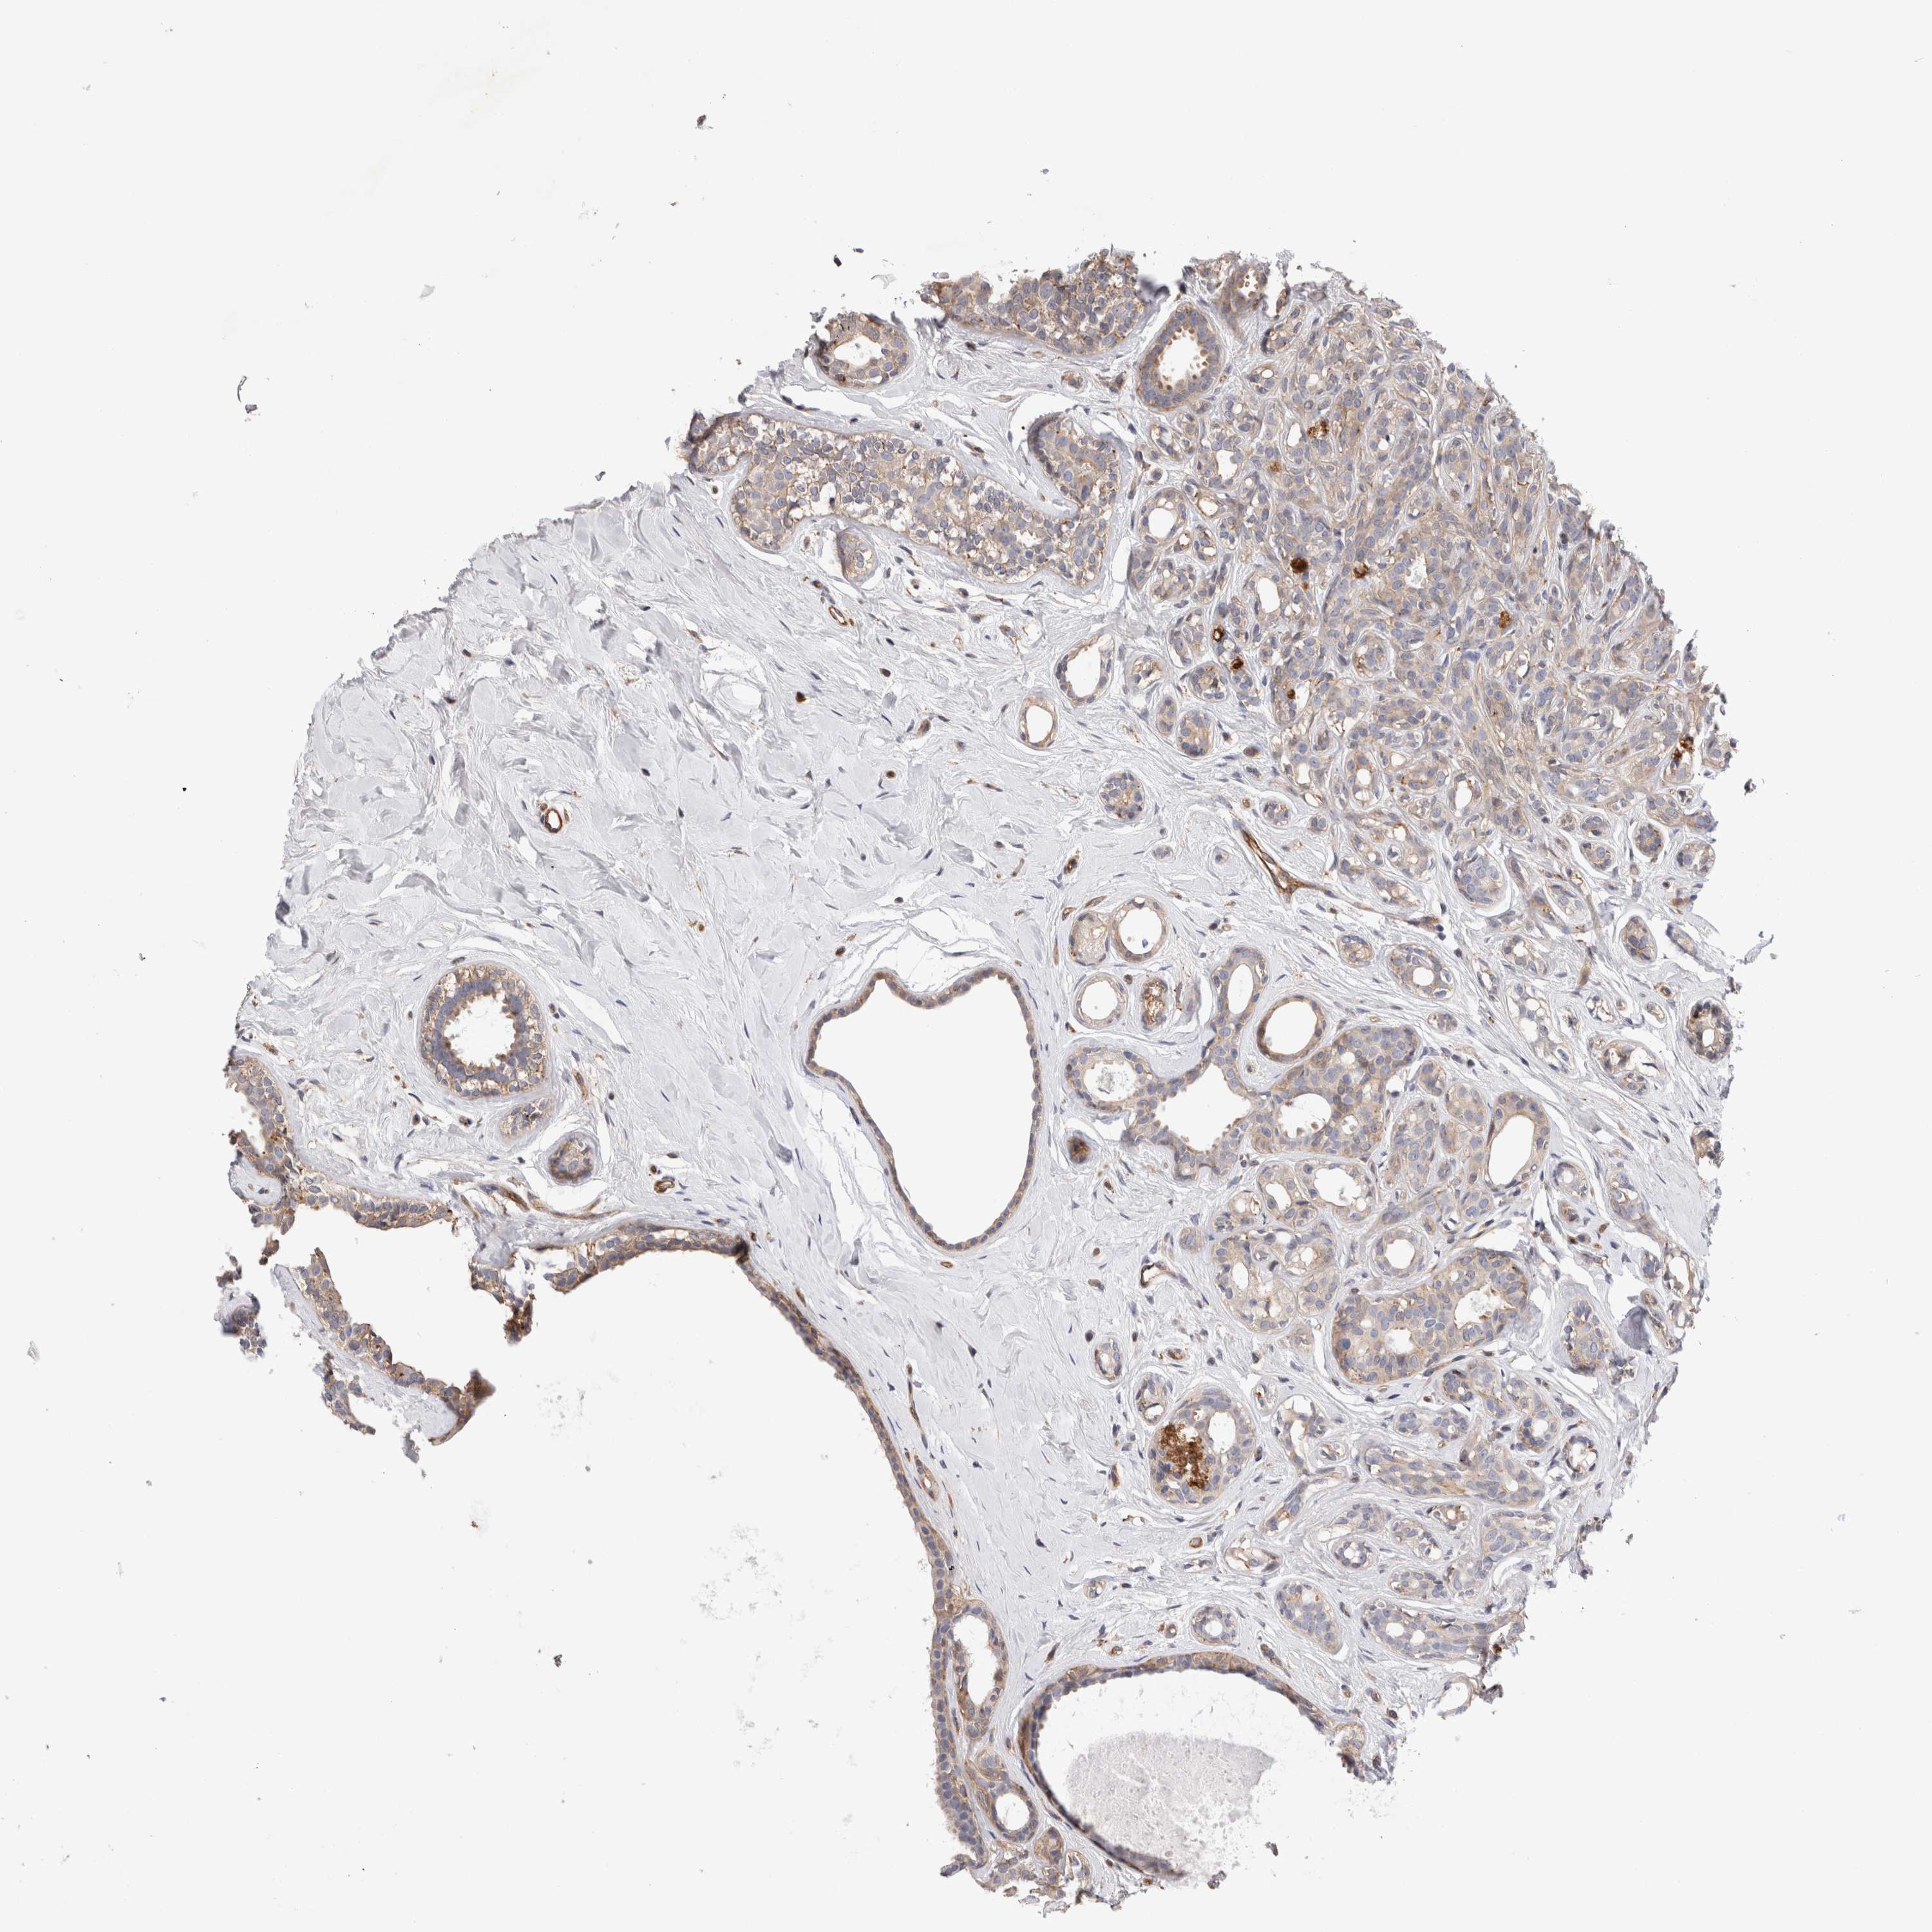

BRCA TCGA BRCA VALIDATION PROTEIN EXPRESSION